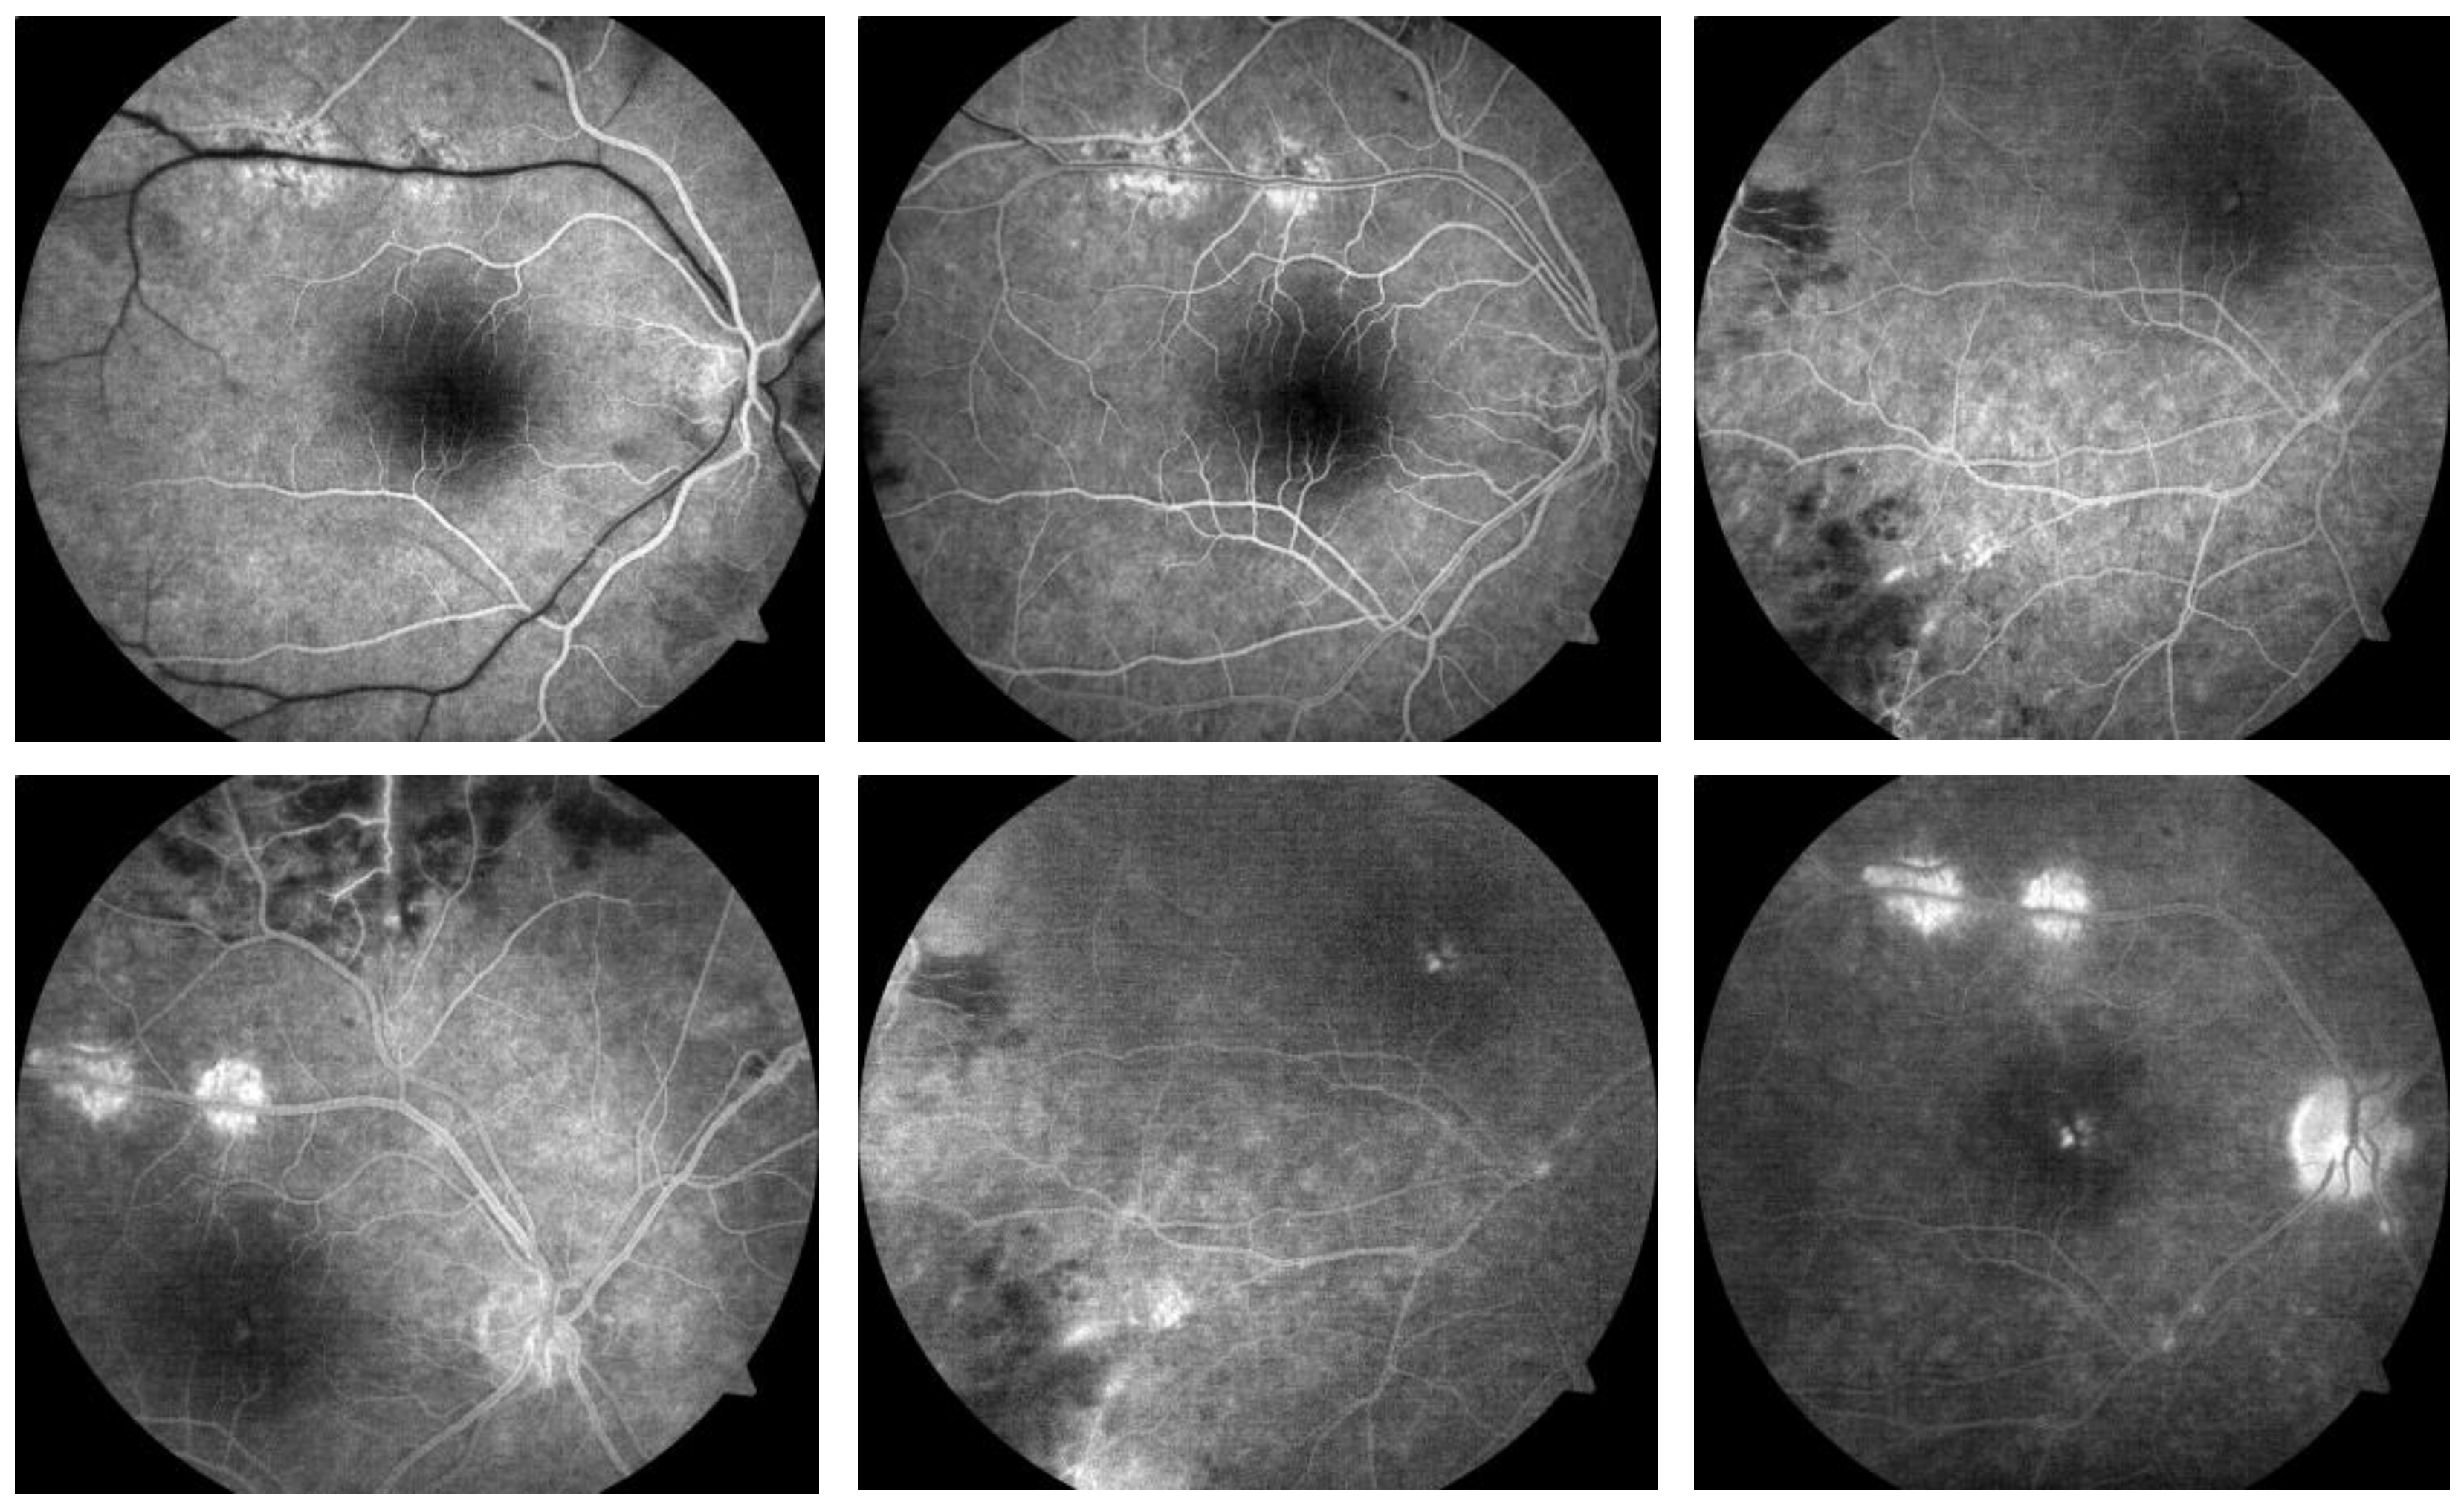

2. Clinical Case Description

2.2. Results of Clinical and Laboratory Examinations